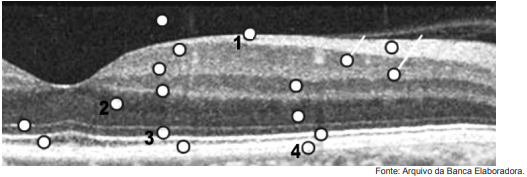

Observe o exame abaixo.

Com relação a esse exame, é correto afirmar que o número